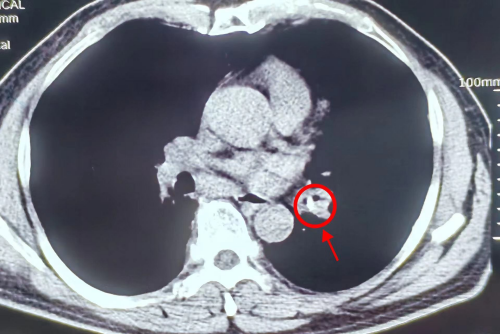

刘建勋家住娄底双峰县,三年前检查出患有慢性支气管炎病史,每次有症状时用点消炎止咳药就会有所缓解。但在最近半个月,刘建勋服用药物后咳嗽、气促症状并无好转,而且出现反复发热、胸痛症状。3月9日,他在家人的陪同下来到香港马会app (南华大学附属香港马会app )呼吸与危重症医学科就诊。呼吸与危重症医学科副主任、副主任医师刘达仔细询问病史,结合CT检查发现他的左下支气管有一块阴影,痰病原学检测为口腔定植菌,考虑支气管异物可能性大,建议刘大爷做一个肺部纤维支气管镜的检查以明确诊断。

(影像检查发现患者的左下支气管有一块阴影)